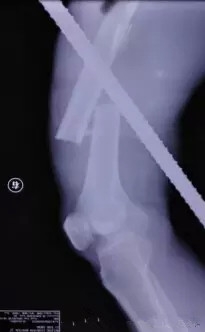

该患者是某工地的建筑工人,施工时因右手未抓紧钢架,从10几米高空坠落地面,被竖在地面上的两根长近2米、直径近4厘米的钢筋插入其体内。其中一根钢筋从下往上穿通在左侧肩胛骨位置,另一根钢筋穿通其右大腿中段。

患者送到医院后,北京积水潭医院急诊医护人员迅速对患者进行心电监护、开放静脉,急配血。经X光检查,胸部的钢筋插在了胸壁上,并未伤及患者胸腔、肺部及大血管。

随后,由创伤骨科孙旭大夫主刀取另外一根钢筋。这根钢筋是从右腿后侧插入体内后从前方穿出,造成患者股骨干骨折,但幸运的是钢筋的走势虽然离重要的血管特别近,但是并未伤及。为了减小二次伤害,孙旭大夫决定采取直接将钢筋拔出的手术方案。

孙旭大夫摸着患者的足背动脉搏动将钢筋从大腿中一点点撤出。在钢筋走形的路径里,采用了外科专用的清洗设备进行伤口清理和清创,同时进行了骨折复位。孙大夫考虑内固定架可能会引起伤口感染风险,于是采用了外固定架,手术持续了近两个小时,顺利完成。患者的生命保住了。